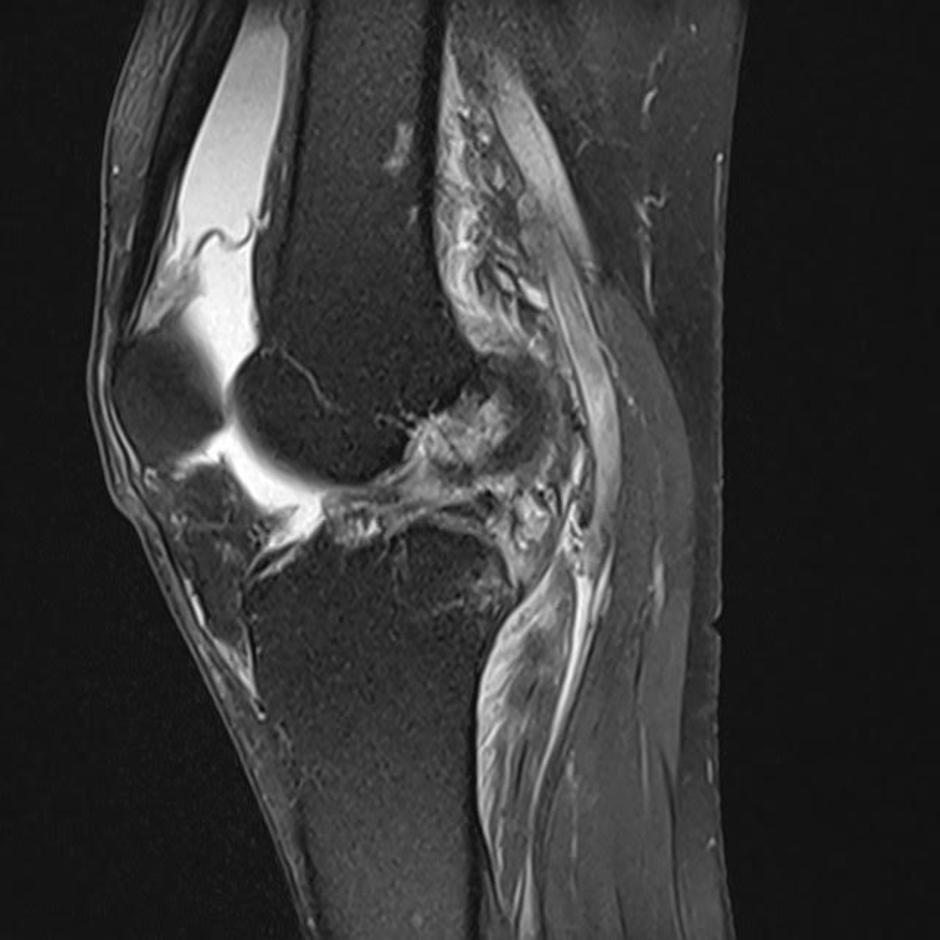

"Pretrganje vezi pomeni, da se zaradi prevelike obremenitve pri športu strga sprednja križna vez, ki je ena od vezi, ki povezujejo stegnenico in golenico v kolenskem sklepu. Pogovorno imenovanje "križnih vezi" se nanaša praviloma ne eno najpogosteje poškodovano: sprednjo križno vez. Posledica popolnega pretrganja te vezi je določena stopnja nestabilnosti kolenskega sklepa, odvisno od tega, kako močne in koordinirane so mišice noge," je pojasnil Macura.

koleno | Avtor: Facebook Facebook

Na vprašanje, ali je v primeru pretrgane križne vezi operacija neizbežna, je dolgoletni zdravnik slovenske košarkarske reprezentance odvrnil: "Ne vedno. Odločamo se glede na stopnjo poškodbe in morebitne pridružene poškodbe kosti, hrustanca, meniskusov, drugih vezi in glede na pričakovano stopnjo aktivnosti oz. funkcionalne zahteve. Po podatkih švedskega registra poškodb kolenskih vezi se kirurgi ob prvem srečanju s pacientom v polovici primerov odločijo za operacijo, v polovici pa za fizioterapijo."

Za konec je pojasnil, zakaj gibanje s takšno poškodbo ne predstavlja nujno velikega tveganja, dokler seveda ne pride do ekstremnih obremenitev, s kakršnimi se je na tekmi srečala Vonnova. "Odvisno od stopnje nestabilnosti in vrste gibanja. Hoja, kolesarjenje, tek na smučeh (sploh klasična tehnika), plavanje in podobni športi so manj nevarni. Pri kompleksnih gibih, ki zahtevajo eksplozivne spremembe smeri, zasuk obremenjene noge, pristanke po skokih ali gibanje po neravnem terenu pa je nevarnost dodatnih poškodb precej večja. Pri teh bolj kompleksnih gibih je potreba po reakciji sklepa v delčkih sekunde in se pozna vsaka malenkost. Z nestabilnim kolenom oz. pretrgano sprednjo križno vezjo so takšne reakcije bistveno upočasnjene, kar lahko privede do dodatnih poškodb."